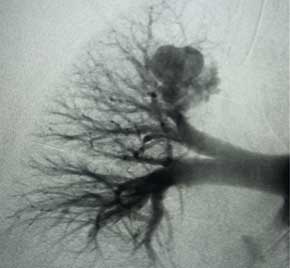

AVM treated with Embold Fibered Coils

Scan of vein before placement of coil. Visualizing the pulmonary artery​

Scan of vein after Embold fibered coil. After Embold Fibered placement​

Bret Wiechmann, MD

HCA Florida North Florida Hospital

Gainesville, FL